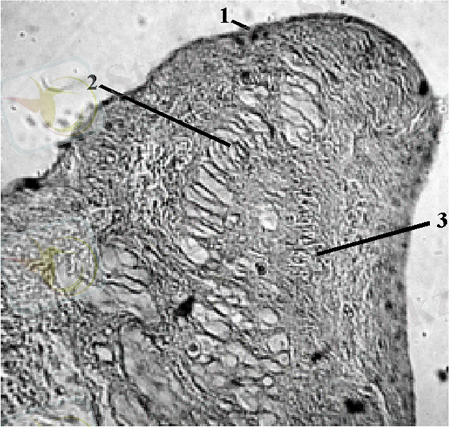

Жүрек түйңінің қабырғасы (1), (2), 3 - жүрек миокард, .

1) Жүрек түйінінің қақпашасы 2) Пуркенье жасушалары 3) каллоген және эластин таошықтары

Жүрек түйінінің қабырғасымен Пуркень жасушалары(1) .